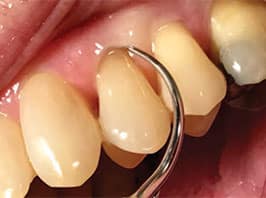

thin diameter and long ultrasonic insert/tip

for light deposit.Figure provided by WILL CLEARY

The lack of bleeding on probing is positive in assessing health.8,10,11 If bleeding on probing is identified, inflammation is present; therefore, it is wise to instrument these areas with extra diligence.12 A careful examination of the bleeding on probing site(s) is indicated to determine if residual calculus or newly formed deposits are present. For either type, a site-specific UIT is needed. For example, bleeding in a deep and narrow 7 mm pocket signals that a very long UIT is indicated to reach the base of the pocket and its corresponding walls. If the calculus is burnished or residual, a wider diameter and long UIT is needed (Figure 2). A “top down” approach with a higher power setting is indicated due to the tenacious and larger deposit (Figure 2), followed by a thinner UIT. However, if light deposit is detected, a very thin diameter and long UIT suffices with the technique described above (Figure 3).